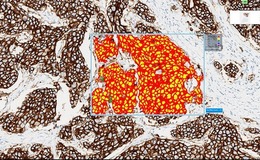

A digital system that allows scientists to scan images of tissue slides and patient histories, attach matching barcodes and upload to a database has been suggested as the future of digital pathology.